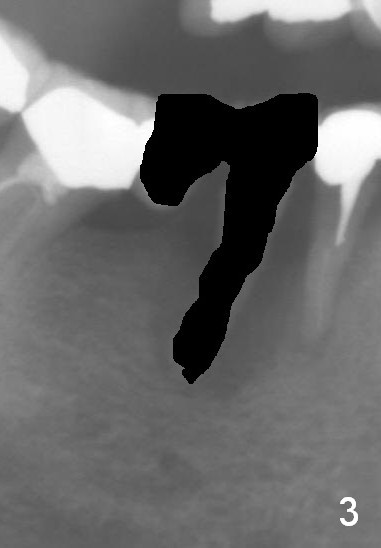

A 50-year-old lady (ZC) has poor dentition (Fig.1). The buccal gingiva of the tooth #29 is erythematous and edematous with deep pockets and severe bone resorption (Fig.2). Two units of the 5-unit bridge is going to be removed (Fig.3). A large implant is to be placed at the site of #29 (socket treated with Metronidazole), while a small one (probably 1-piece) at #30 (narrow mesiodistal space, Fig.4 green outlines). Be care of the mental loop (red dashed line). In fact, the patient wants to have #3 implant placed first.